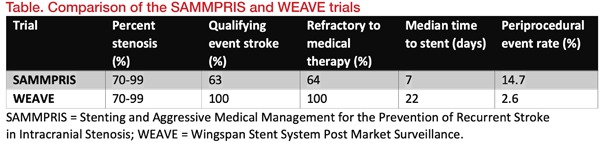

Significance of the WEAVE trial“The WEAVE trial is important to neurologists as it identifies the target population for Wingspan stent treatment and addresses perioperative safety issues,” said Miao. Yu agreed: “The WEAVE trial showed that stenting for ICAD is not as dangerous as SAMMPRIS showed,” referring to the Stenting versus Aggressive Medical Therapy for Intracranial Arterial Stenosis trial. [N Engl J Med 2011;365:993–1003] This trial evaluated patients in an extended clinical application of the Wingspan stent, beyond its approved FDA labelling. This included stenting patients who had not failed medical therapy, those who may have presented with transient ischaemic attacks only, without history of stroke, and stenting patients earlier than 8 days after their qualifying event. Notably, the majority of patients stented in the SAMMPRIS trial did not meet the on-label indication, which resulted in a periprocedural stroke, bleed, and death rate of 14.7 percent. [N Engl J Med 2011;365:993–1003] In contrast, in the WEAVE trial, the periprocedural event rate was just 2.6 percent for on-label patients (Table). [Stroke 2019;50:889-894]

“The SAMMPRIS trial showed high periprocedural complication rate for ICA stenting. This is a large barrier to perform intracranial artery stenting. Fortunately, the WEAVE trial showed that this high periprocedural complication can be reduced depending on the time of ICA stenting and the experience of ICA stenting. These results opened up the possibility that stent treatment may be reintroduced to ICAD treatment,” said Seo.

Since its introduction in 2005, the design of the Wingspan stent has not changed substantially except for modifications of the radio-opaque markers. Therefore, the WEAVE results imply that the high periprocedural seen in the SAMMPRIS trial were unlikely to be due to issues with the stent itself, but probably stemmed from a combination of factors, such as interventionalists’ lack of experience, poor patient selection, and underdeveloped standards of practice in intracranial stenting. “The different results from the WEAVE trial vs SAMMPRIS make neurologists more confident to consider the use of the Wingspan stent to treat selected ICAD patients,” said Wong.